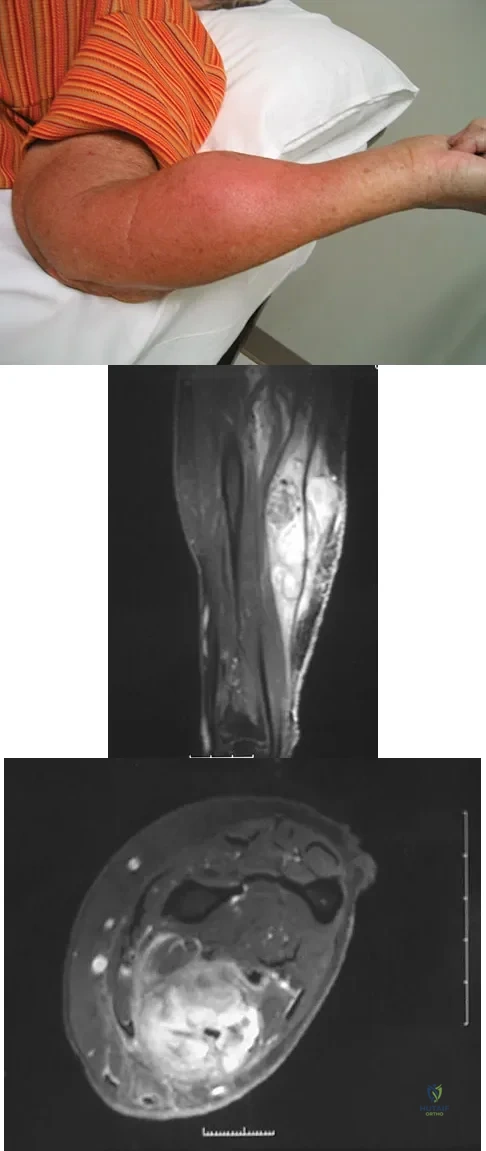

Figure 8a shows the clinical photograph of an 83-year-old woman who has an enlarging left forearm mass. MRI scans are shown in Figures 8b and 8c. What is the next most appropriate step in management?

Explanation

An 18-year-old boy reports increasing pain with weight bearing on his right leg and at night. Examination reveals swelling around the right midcalf. Radiographs and an MRI scan are shown in Figures 13a through 13c, and a biopsy specimen is shown in Figure 13d. What is the preferred treatment?

Explanation